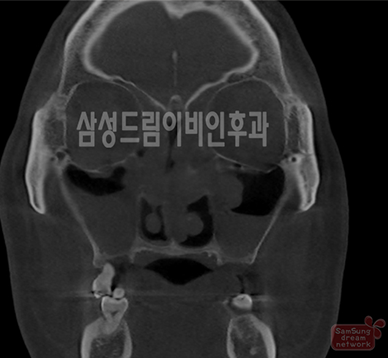

축농증 소견 코CT, 정상 소견 코CT

삼성드림의 축농증 내시경 수술

내시경을 이용하여 염증이 있는 부비동을 개방하여 환기와 배설이 이루어지도록 하고, 원인이 될 수 있는 코 안의 구조적 이상을 교정하는 것입니다.

외부의 흉터가 남지 않고 수술 후 통증이나 합병증이 최소화 된 수술법입니다